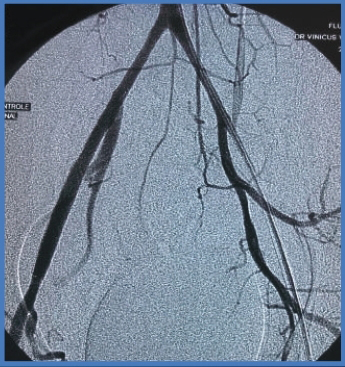

Clinical Case, EIA lesion

PREPOST